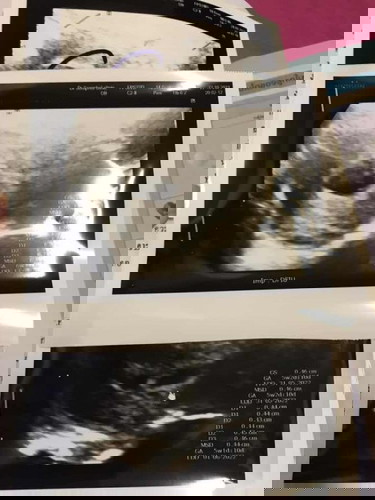

ถามแม่ๆหน่อยได้ไหมค่ะใครเคยมีประสบการณ์แบบนี้บ้างค่ะ ตอนนี้น้องได้ 10สัปดาห์แล้ว แต่พอซาวออกมาหมอบอกน้องไม่โต ไห้เราไปขูดมดลูก แต่อาการเราไม่เป็นอะในเรยค่ะ แถมยังคงแพ้ท้องยุด้วย เป็นไปได้ไหมค่ะว่าน้องไม่เป็นอะใร#ใครมีประสบการณ์ #ขอบคุณสำหรับคำตอบค่ะ